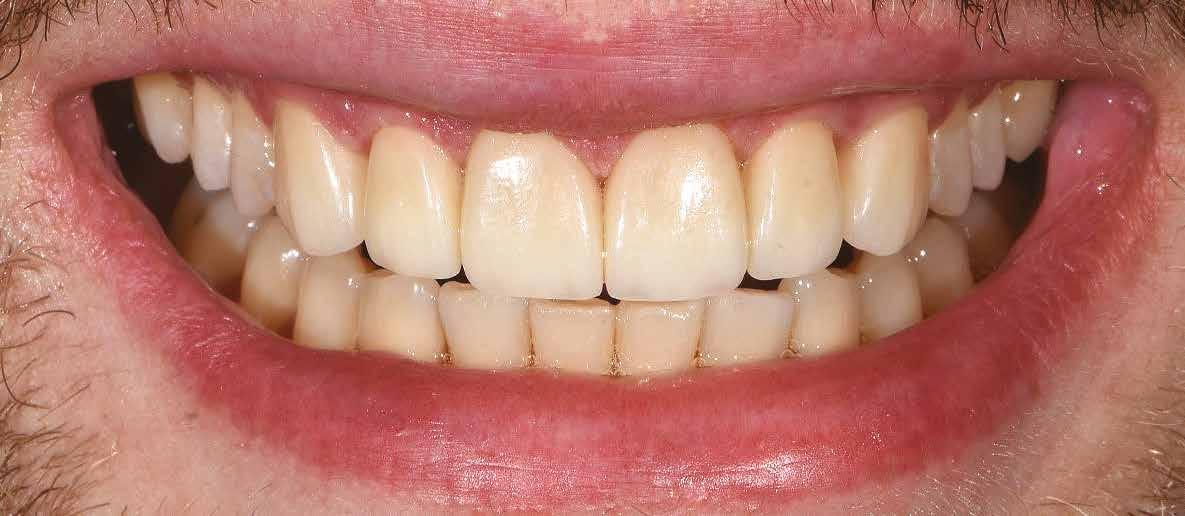

A 26 éves férfi páciens azzal a kéréssel kereste fel a rendelőnket, hogy a frontfogai esztétikusabb megjelenését szeretné elérni. A páciens jó általános egészségi állapottal rendelkezett, nem szenvedett allergiáktól és nem kellett rendszeresen gyógyszereket szednie. A páciens lehetőség szerint kerülte a fogai megmutatását. Rendkívül zavarónak találta a nagymetszői között, a középvonalnak megfelelően látható rést, a fogain látható kopási jeleket, valamint a fogai méretét is túl kicsinek találta. A szájüregi vizsgálat során megállapítottuk, hogy a nagymetsző fogai (11, 21) élharapásban vannak, valamint az alsó fogíven kismértékű torlódást észleltünk. A felső frontfogakon

(13-23) attrícióra utaló jeleket találtunk. A fogak kopása a nagymetszőfogaknak megfelelően volt a legkifejezettebb (1. ábra) . Az előbbiekben említett fogak (11, 21) ezen kívül némileg elfordultak, és jelentősebb méretű diasztéma volt köztük. A páciens Angle I.-osztályú állcsontrelációs helyzettel rendelkezett. A vizsgálat során feltűnt, hogy a páciens csak nagyon óvatosan mert mosolyogni (2. ábra)

A szájüregi vizsgálat során nem találtunk szuvas léziók jelenlétére utaló eltéréseket. A nagymetszőfogakon megfigyelhető jelentős mértékű kopás ellenére nem észleltünk craniomandibuláris diszfunkció jelenlétére utaló jeleket. A vizsgálat befejezését követően a pácienst tájékoztattuk a különböző kezelési lehetőségekről. Az esztétikai megjelenés javítása érdekében először egy alignerekkel végzett fogszabályzó kezelés elvégzését, majd a harapási helyzet optimalizálását követően a felső frontfogai kompozittal történő direkt felépítését vagy héjakkal történő ellátását (pl.: non-prep héjak) javasoltuk (3. és 4. ábra).

A fogazat minimálinvazív módon készített héjakkal történő ellátásához a fogaknak olyan pozícióban kell lenniük, amely lehetővé teszi az esztétikai megjelenés additív eljárások alkalmazása mellett történő optimalizálását.1. ábra: Kiindulási állapot. A felső nagymetszőfogak élharapásban vannak. 2. ábra: Az orthodonciai kezelés megkezdése előtt készített intraorális felvétel. A páciens csak óvatosan mer mosolyogni. 3. és 4. ábra: Digitálisan megtervezett kezelés.

A kezelések második fázisában a pácienssel közösen non-prep/ minimálinvazív héjak készítése mellett döntöttünk (6. és 7. ábra).

A páciens teljesen elégedett volt a kezelések befejezését követően elért esztétikai végeredménnyel (9. ábra). A terápiás erőfeszítéseink eredményeinek köszönhetően újra képes felszabadultan nevetni és mosolyogni. A cikkben bemutatásra kerülő eset jól példázza a multidiszciplináris beavatkozások alkalmazásában rejlő előnyöket. A megfelelő sorrendben végzett orthodonciai és restauratív kezelésekkel lehetővé vált a páciens mosolyának minimálinvazív módszerekkel történő optimalizálása. A körültekintő tervezésnek köszönhetően nem került sor felesleges beavatkozások elvégzésére, és emiatt a kezelések befejezéséhez szükséges idő sem nyúlt a szükségesnél hosszabbra. Arra is felhívnánk a figyelmet, hogy a jól megszervezett, továbbá a lehető legkevesebb rendelési időt felhasználó kezelések – a beavatkozásokat végző fogorvosok számára is – rendkívül kedvezőek lehetnek.